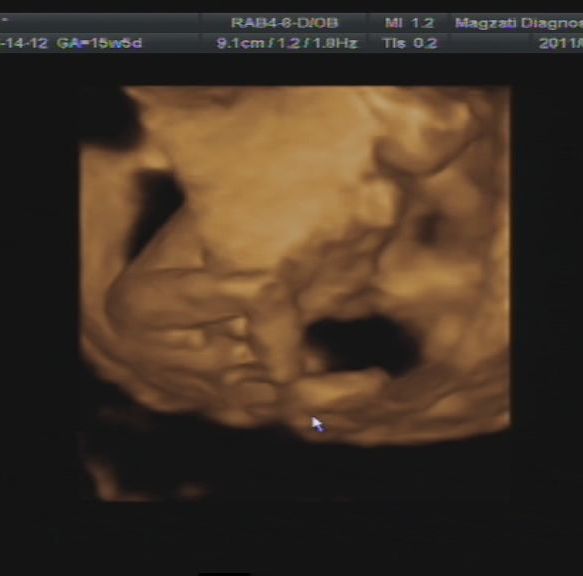

18+6

kuki

Ki is van odabent